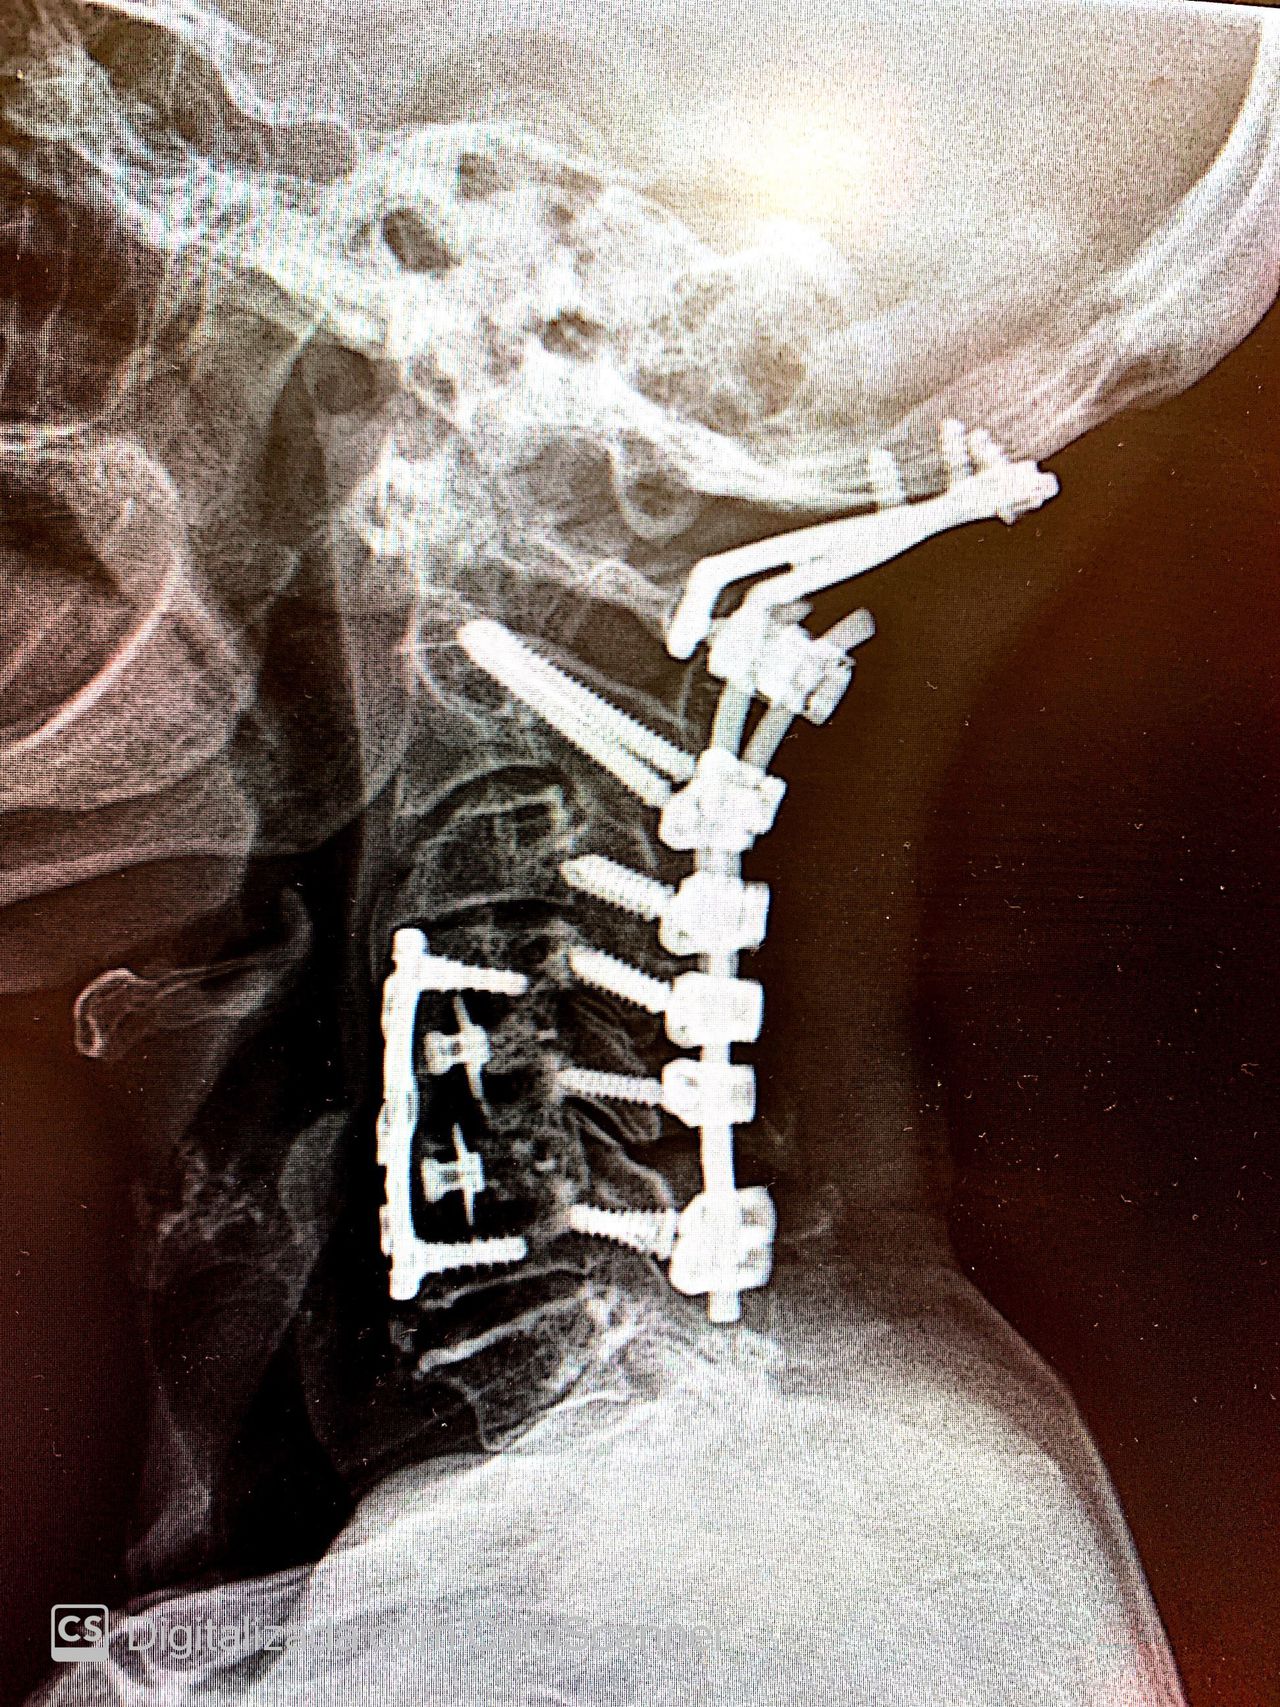

• Cirurgia da coluna cervical

Com mais de 2000 cirurgias realizadas, formação pela USP e especialização na Alemanha, Coréia do Sul e EUA, Dr Henrique é Cirurgião Especilista em Coluna há mais de 10 anos, se dedicando em trazer qualidade de vida às pessoas que sofrem com Hérnia de Disco, Espondilolistese, Escoliose, Cifose de Scheuermmann e Fraturas da Coluna, Dor Ciática, Lombar e Cervical.